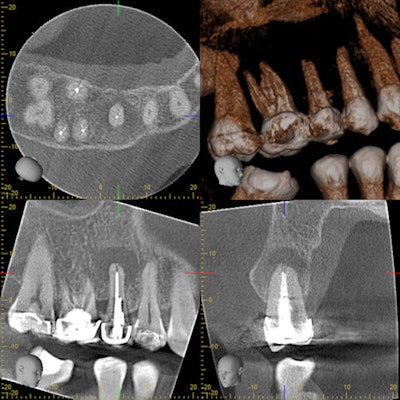

The CBCT indicates an acute apical abscess on a prior endodontically treated tooth.Dr. Deepika Ganne.

Incision and drainage help when fluctuant swelling is seen. Root canal therapy in two visits with calcium hydroxide as intracanal medicament is preferred. Anti-inflammatory medications and antibiotics are prescribed.